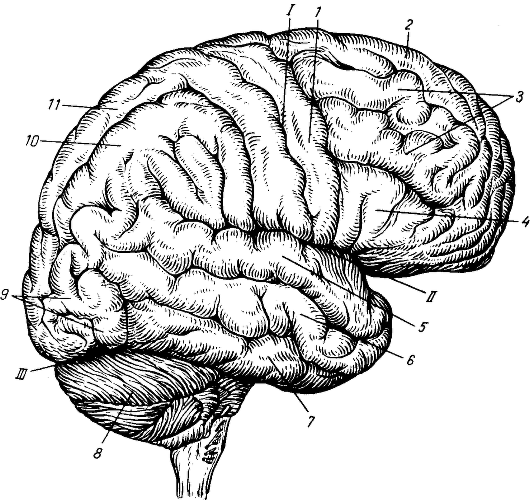

Легкие рисунки головного мозга: Пошаговые инструкции